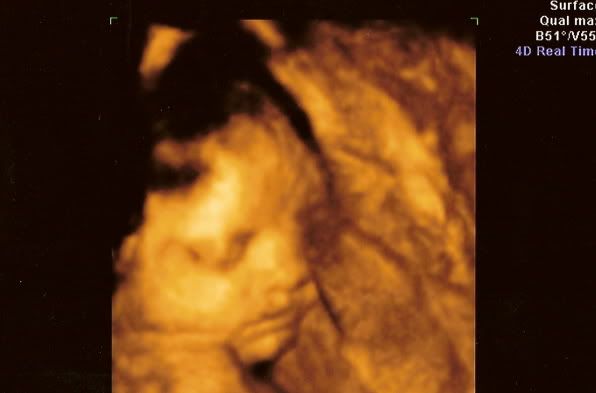

Hannah Banana while she was still in my uterus...![]() Another shot....

It was amazing. Everyone was there...My mom, grandma, aunt, Paul's parents, Paul and Hayden. We were all thrilled with the first real images of Hannah. When we first saw her face on the screen, my mom said, "My Gosh Tassy! She looks just like you!!!" |

Isn't it unreal what they can do with technology today? Of course this 4D ultrasound cost us a pretty penny but it was worth it. We got about 45 pictures and 30 minutes of video. When she was born everyone was comparing the ultrasound pics with what she really looked like. This technology wasn't available in 1999 when I was pregnant with Hayden. |

Them pictures are amazing Tassy! I'm going to have a 4D scan done in a month and that is A LOT over here but it will be worth it and you get 100 photos, an hour appointment and a 45 minute dvd of the baby so I can't wait!